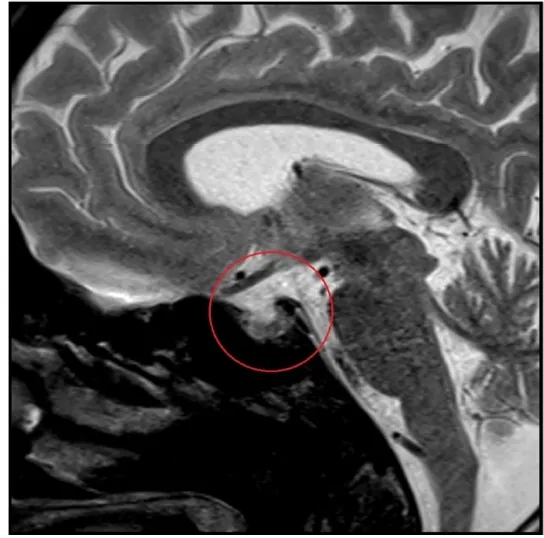

Uma causa incomum de hematúria glomerular intermitente!

Uma causa incomum de hematúria glomerular intermitente!

Hematúria pós infecção, caso clínicos para auxiliar no entendimento de causas glomerulares comuns e raras...